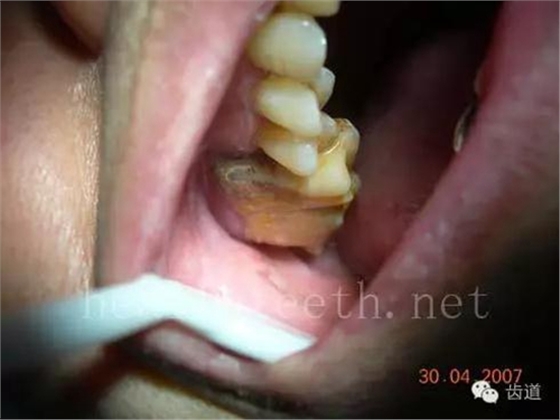

青少年牙周炎,20多歲牙齒破壞到這個程度